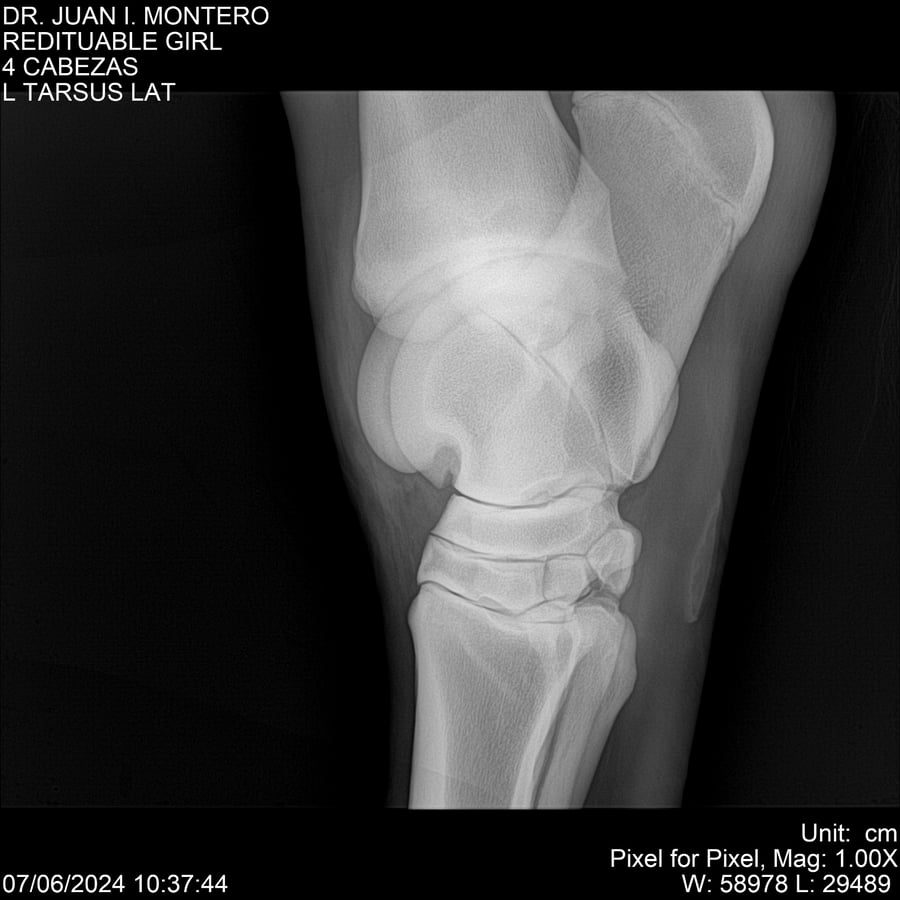

LOTE 19, REDITUABLE GIRL Lote Anterior Volver al remate Lote Siguiente Ficha Contacto Montevideo - Ficha del Lote Identificador: #281096 Categoría: Yeguarizos Montevideo - 79 Visualizaciones ClicData Contacto Empresa: Abelenda N. R., Walter Hugo Nombre*: Teléfono* : E-mail* : Mensaje Enviar Registrese gratis Este contenido Exclusivo está disponible sólo para usuarios registrados Ingresar